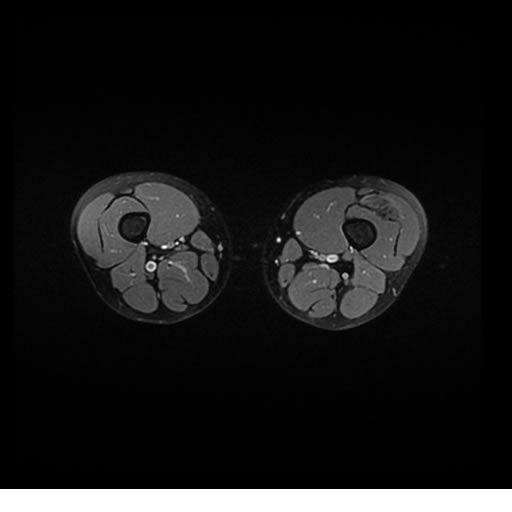

Se realiza estudio de MRI de pierna izquierda, utilizando secuencias Spin Echo y GRE en diferentes planos, se realiza angio MRI en fase arterial y venosa de pierna izquierda

El estudio demuestra masa a nivel de los músculos gemelos, más evidente en secuencia con pulso de saturación de grasa, en el estudio de angio resonancia de pierna la fase arterial no muestra ninguna anormalidad, en la fase venosa se observa acumulo del medio de contraste a este nivel.

Se concluye que se observa una masa de tejido muscular sumamente vascularizada compatible con un hemangioarcoma.